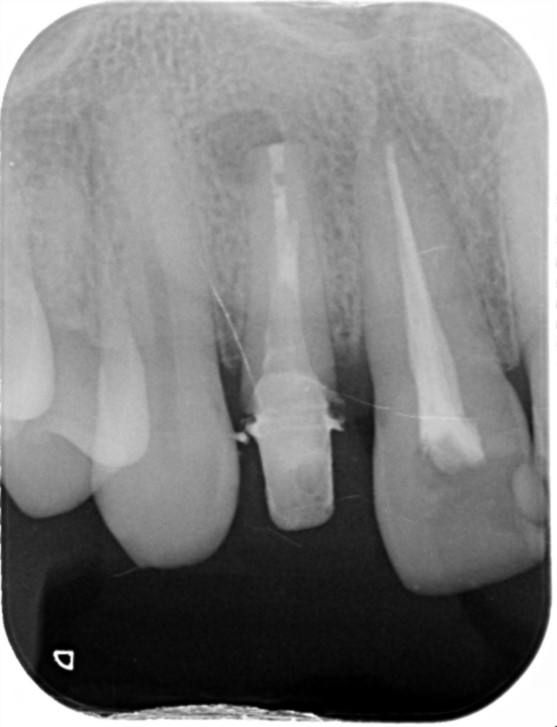

2023.1/25 他院で被せ物を作成した歯が腫れて痛みがあるということでご来院。

2024.6/5 被せ物は外し、当院で改めて根っこの治療を行いました。

2024.9/5 右上2番の治療が終わり、ジルコニアクラウンの被せ物を作成しました。

治療部位 | 右上2番 |

---|---|

費用 | 保険分+自費で約11万円 |

治療期間 | 21ヶ月 |

注意事項(リスク・副作用など) | 治療の刺激や薬剤の刺激により、治療後数時間から数日後に痛みや腫れが生じる場合があります。 |

カテゴリ | 歯内療法 |